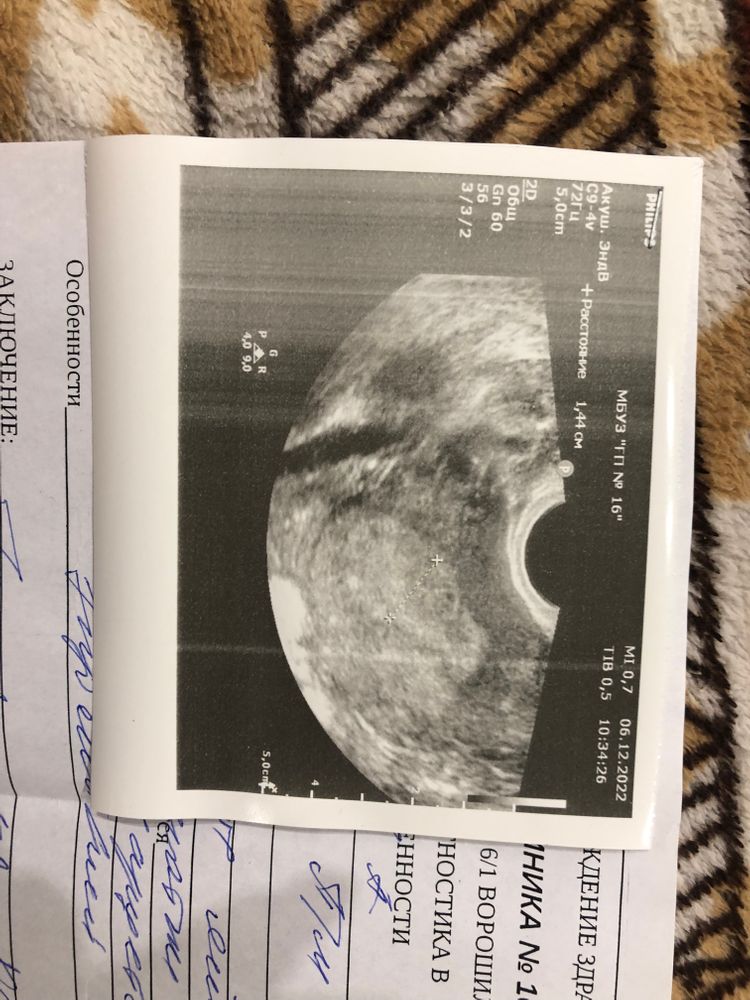

Enotik Lesnoy , Изображение

07.12.2022

Анастасия, очень странно. Может в хгч ошибка? Эндометрий хороший. Переделайте узи и хгч.. пусть найдётся малыш

Анастасия, добрый вечер! Это наша дорогая 16я поликлиника😅 у меня на этом сроке тоже не увидела врач,в железке делала платно на следующий день и сердце нашли и ктр померяли

Анастасия, так что не беспокойтесь всё хорошо,дома такая же бумажка лежит и врач эта же